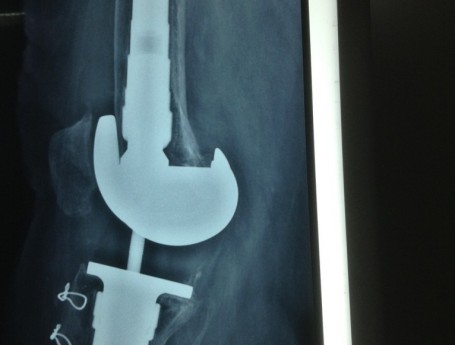

Revision Total Knee Replacement After a fructure

Revision Total Knee Replacement After Infection

Total Knee Replacement